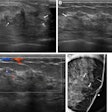

Although breast ultrasound is useful for differentiating masses, the morphologic features of benign and malignant lesions have substantial overlap. Interpretation of these images depends greatly on radiologist experience, leading to the potential for significant interobserver variability, according to the researchers.

As a result, they sought to train a convolutional neural network (CNN) to distinguish between benign and malignant breast masses on ultrasound studies. The researchers retrospectively collected 480 images of 97 benign masses and 467 images of 143 malignant masses for use in training. The deep-learning model, which was developed using the GoogLeNet CNN architecture, was then tested on a set of 120 images of patients with 48 benign masses and 72 malignant masses.